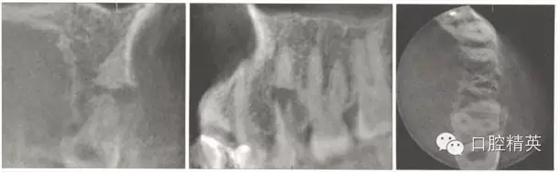

X線片示:上頜第二前磨牙根中部折斷,斷端呈喇叭口狀。斷端根尖段根管影像消失,牙周膜間隙未見明顯異常,斷端根中上段根管粗大,斷端周圍弧形低密度影像(圖2)。牙膠示蹤片示瘺管來源于斷端。

圖2初診X線片。

錐形束CT示:斷端處根中上部和下部完全分開,斷端根尖部未見根管影像。斷端呈喇叭口狀,斷端的近遠(yuǎn)中側(cè)均有骨質(zhì)破壞(圖3)。

圖3 初診錐形束CT影像